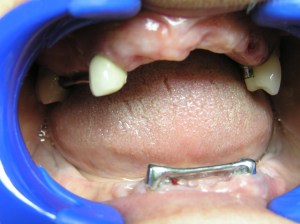

Klizač u gornjoj vizil protezi

Klizači u donjoj vizil protezi

Drugi tip najčešće korišćenih atečmena su klizači, koji funkcionišu po istom principu. Lepota i umetnost izrade vizil proteza sa atečmenima je u mnogobrojnim kombinacijama koje se mogu izvesti samo uz pomoć ova dva tipa atečmena. Klizači i kuglice se mogu koristiti na krunicama izrađenim na preostalim zubima, na korenovima preostalih zuba, na zubnim implantima, a mogu se i pojedini zubi povezati sa prečkama i na njima postaviti neki od ovih atečmena. To se posebno preporučuje kada je preostao mali broj zuba, a želi se postići maksimalan učinak proteze.

Preostali zubi su povezani prečkama a preko njih se spajaju proteze sa klizačima